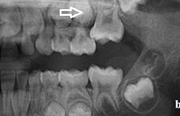

Esimeste molaaride (purihammaste) lõikumine

Esimeste molaaride (purihammaste) lõikumine. 1. molaaride ektoopilise lõikumise jälgimine. Ülemised ja alumised esimesed purihambad e. molaarid lõikuvad orienteeruvalt6-7-aastaselt piimahammaste rea lõppu. Enamasti lõikuvad samanimelised jäävhambad paaridena. Normaalne lõikumise Loe edasi »

Sümptomid:

- valehambumus (18)